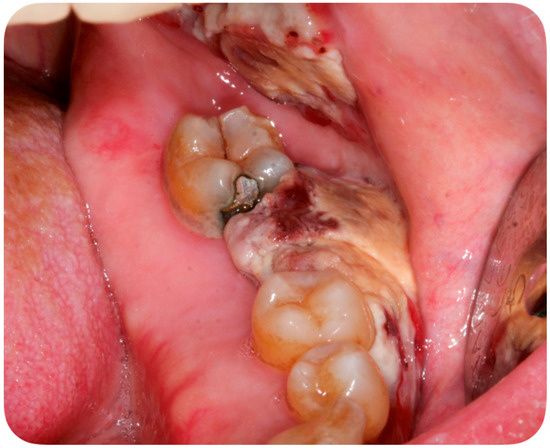

A 56-year-old Caucasian man affected by acute myeloid leukemia (AML) was admitted to the Hematological Department of Policlinico A. Gemelli (Rome, Italy) for febrile neutropenia with multiple oral swellings. The patient’s medical history revealed previous diagnoses of myelodysplastic syndrome (2016), refractory anemia with excess blasts type 1 (RAEB-1), which was treated with ten cycles of decitabine and an allogenic hematopoietic stem cell transplantation. This recurring disease evolved into Acute Myeloid Leukemia (2018). Consequently, re-induction chemotherapy was administered using Chlorambucil and Cytarabine first, followed by a combination of Azacitidine and Venetoclax. In October 2019, the patient was hospitalized for febrile neutropenia with severe thrombocytopenia. At that moment, the patient was receiving antifungal prophylaxis with Posaconazole 300 mg/die. Blood culture was performed and the research for yeasts was negative. The physical examination did not retrieve any skin lesion. The oral examination revealed that three rapidly growing asymptomatic ulcerated swellings, located on both the buccal mucosa and the left mandible, arose 15 days before (Figure 2, Figure 3 and Figure 4).

Figure 2. Asymptomatic ulcerated lesion, located on the right buccal mucosa.

Figure 4. Asymptomatic ulcerated lesion, located on the left mandible.

Lesions were light-grayish in color, friable, with a 4 cm diameter, and protruded from the mucosa, interfering with chewing. After a platelet transfusion and local anesthesia (Carbocaine 2% with epinephrine 1:100,000; Dentsply, Verona, Italy), an incisional biopsy was performed together with a microbiological sampling for fungi. The pathology revealed an inflammatory process in association with purulent necrosis and microbial colonies; no granulomas were detected in the specimen. Part of the sample was discharged in liquid Amies medium, then streak-plated on Sabouraud dextrose agar plates supplemented with gentamicin and chloramphenicol (Bio-Rad, Hercules, CA, USA) and BBL CHROMagar Candida plate (BD). We identified species using Bruker Biotyper version MBT 3.1 matrix-assisted laser desorption/ionization time-of-flight (MALDI-TOF) mass spectrometry (Bruker) and nucleotide sequence analysis of the internal transcribed spacer (ITS) regions of the rRNA gene. Microbiological sampling was thus positive for S. clavata, thus the final diagnosis indicated an intraoral fungal infection due to S. clavata. The Minimal inhibitory concentrantions (MICs) of antifungal drugs were determined in parallel according to the European Committee on Antimicrobial Susceptibility Testing (EUCAST) standardized broth microdilution method [27].

This case report describes the first case of oral lesions as the first manifestation of S. clavata infection and the literature review did not find any other case with oral involvement, thus differential diagnosis was particularly demanding. The infection manifested as three rapidly growing asymptomatic ulcerated swellings, located on both the buccal mucosa and the left mandible, that arose 15 days before. Lesions were light grayish in color, friable, with a 4 cm diameter, and protruded from the mucosa, interfering with chewing (Figure 1). Since clinical presentation of common and rare diseases can be really unusual in immunosuppressed patients, the diagnosis of these lesions was particularly challenging, but some clinical characteristics drove the differential diagnosis: rapid growth, ulcerating feature, bilateral onset, and absence of any other symptom (i.e., pain, itching, burning sensation). For these reasons, oral or deep fungal infections, other opportunistic infections, relapses, or new onset of hematological diseases and granulomatous diseases have been considered in the differential diagnosis (Table 3).